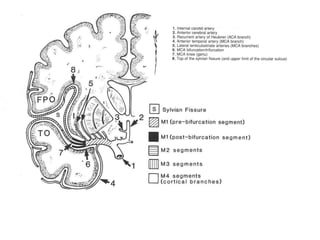

Segmentação da ACM

• M1 (esfenoidal): inicia na origem da ACM e termina em

uma curva de 90 graus (joelho), na junção dos

compartimentos esfenoidal e operculoinsular. É

subdivido em seguimento pré-bifurcação e pós-

bifurcação (proximal ao joelho).

• M2 (insular): começa no joelho, onde a ACM passa

sobre o límen da ínsula e termina no sulco circular da

ínsula, a maior ramificação acontece distalmente ao

joelho, terminam no topo do sulco circular, consistindo

em 6 a 8 artérias tronco principais.

• M3 (opercular): começa no sulco circular da ínsula e

termina na superfície do sulco lateral, estão

intimamente relacionados a superfície dos opérculos

frontoparietal e temporal. Se curvão 180 graus

formando alças.

• M4 (cortical): composto por ramos que se dirigem para

a convexidade lateral. M1 se bifurca em 6 a 8 artérias

tronco principais por hemisférios, cada tronco individual

(segmento M2 ou M3) origina tipicamente de um a

cinco ramos corticais (M4), divididos em grupos

anterior, intermediário e posterior.